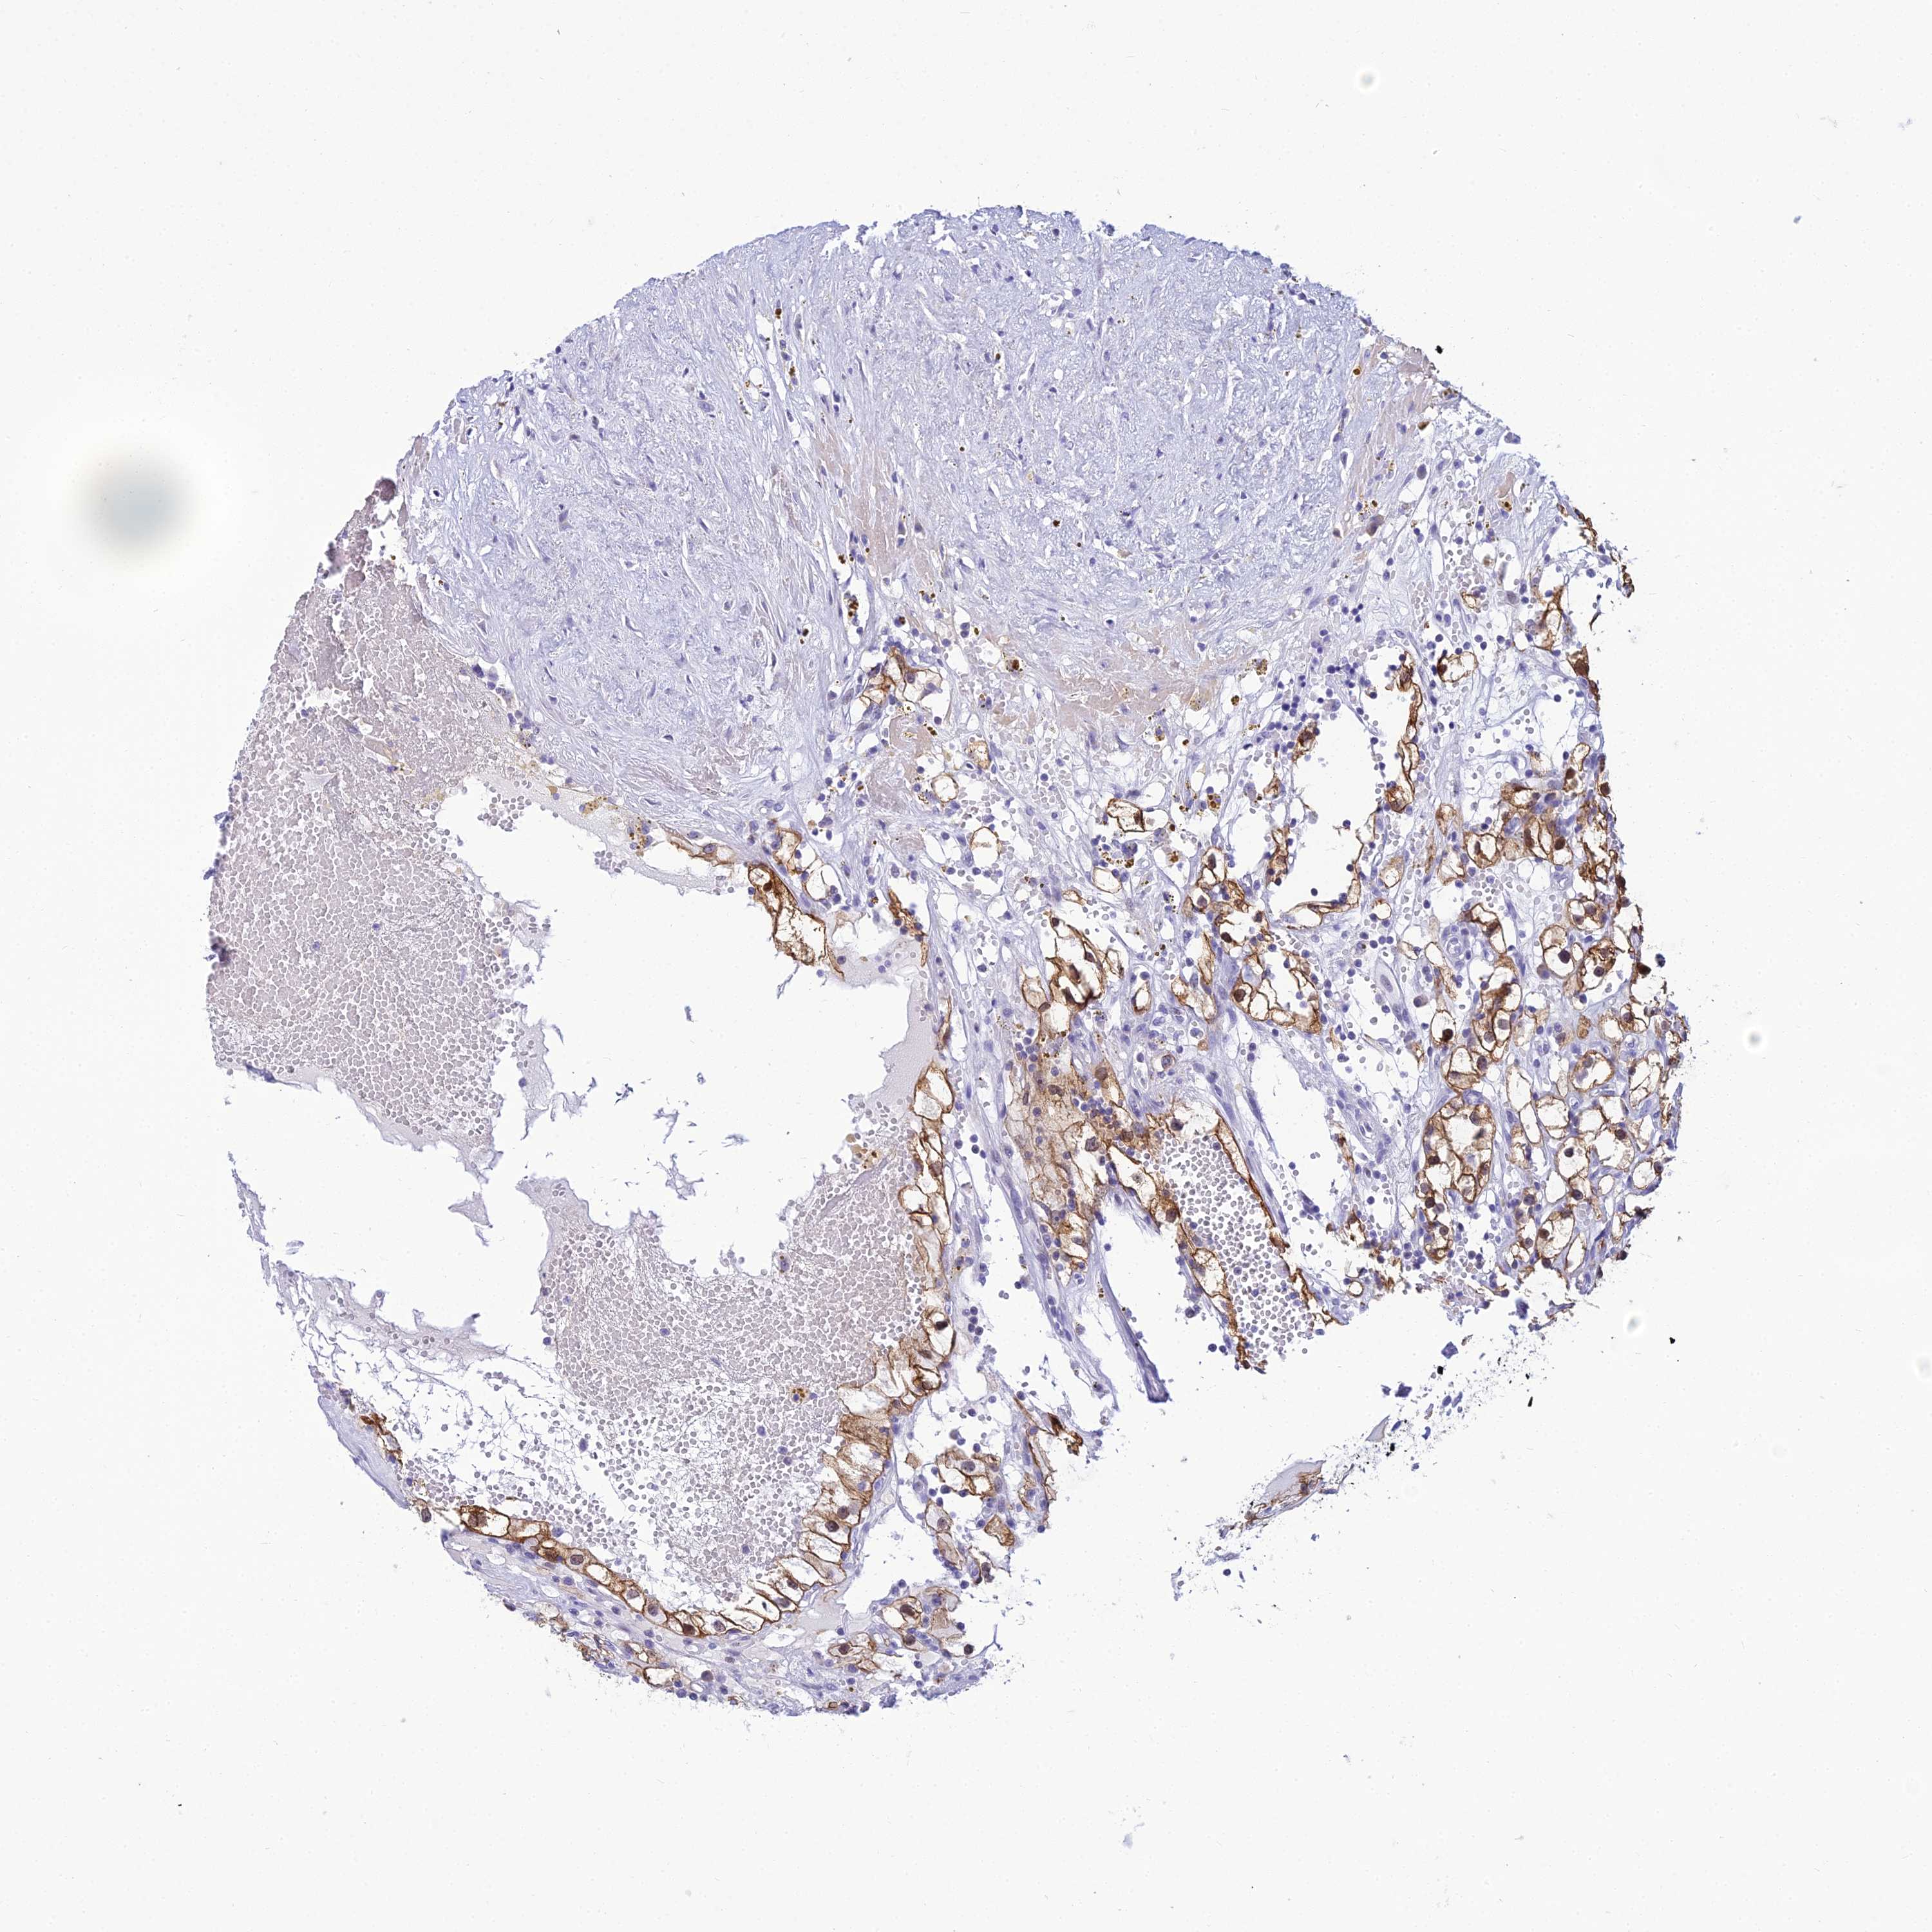

KIDNEY RENAL CLEAR CELL CARCINOMA (VALIDATION) - Interactive survival scatter ploti

The Survival Scatter plot shows the clinical status (i.e. dead or alive) for all individuals in the patient cohort, based on the same data that underlies the corresponding Kaplan-Meier plots. Patients that are alive at last time for follow-up are shown in blue and patients who have died during the study are shown in red.

The x-axis shows the expression levels (FPKM) of the investigated gene in the tumor tissue at the time of diagnosis. The y-axis shows the follow-up time after diagnosis (years). Both axes are complimented with kernel density curves demonstrating the data density over the axes. The top density plot shows the expression levels (FPKM) distribution among dead (red) and alive patients (blue). The right density plot shows the data density of the survived years of dead patients with high and low expression levels respectively, stratified using the cutoff indicated by the vertical dashed line through the Survival Scatter plot. This cutoff is automatically defined based on the FPKM cutoff that minimizes the p-score. The cutoff can be changed by dragging the vertical line or by entering a cutoff value in the square labeled "Current cut-off".

Under the Survival Scatter plot the p-score landscape (black curve; left axis) is shown together with dead median separation (red curve; right axis). Dead median separation is the difference in median mRNA expression between patients who have died with high and low expression, respectively. It is calculated as follows: median FPKM expression of dead patients with high expression - median FPKM expression of dead patients with low expression. This is intended to aid the user in visually exploring custom cutoffs and the associated p-scores and dead median separation.

Individual patient data is displayed and can be filtered by clicking on one or more of the category buttons on the top of the page. Categories describing expression level and patient information include: high, low, alive, dead, female, male and tumor stages. The scale of the x-axis can be toggled between linear and log-scale by clicking on the "x log" button. Mouse-over function shows TCGA ID, patient information and mRNA expression (FPKM) for each patient.

& Survival analysisi

Kaplan-Meier plots summarize results from analysis of correlation between mRNA expression level and patient survival. Patients were divided based on level of expression into one of the two groups "low" (under cut off) or "high" (over cut off). X-axis shows time for survival (years) and y-axis shows the probability of survival, where 1.0 corresponds to 100 percent.

ZMIZ1 is not prognostic in Kidney Renal Clear Cell Carcinoma (validation)

Best expression cut offi

Based on the FPKM value of each gene, patients were classified into two groups and association between prognosis (survival) and gene expression (FPKM) was examined. The best expression cut-off refers the FPKM value that yields maximal difference with regard to survival between the two groups at the lowest log-rank P-value. Best expression cut-off was selected based on survival analysis .

When clicking on this number, the vertical dashed line indicating cut-off, the interactive survival plot, and the Kaplan-Meier curve will be adjusted to show results based on the best expression cut-off.

: 39.18

TCGA RNA samplesi

RNA-seq data is reported as average FPKM (number Fragments Per Kilobase of exon per Million reads), generated by the The Cancer Genome Atlas (TCGA) .

Normal distribution across the dataset is visualized with box plots, shown as median and 25th and 75th percentiles. Points are displayed as outliers if they are above or below 1.5 times the interquartile range. FPKM values of the individual samples are presented next to the box plot.

Average pTPM 31.9

Number of samples 100